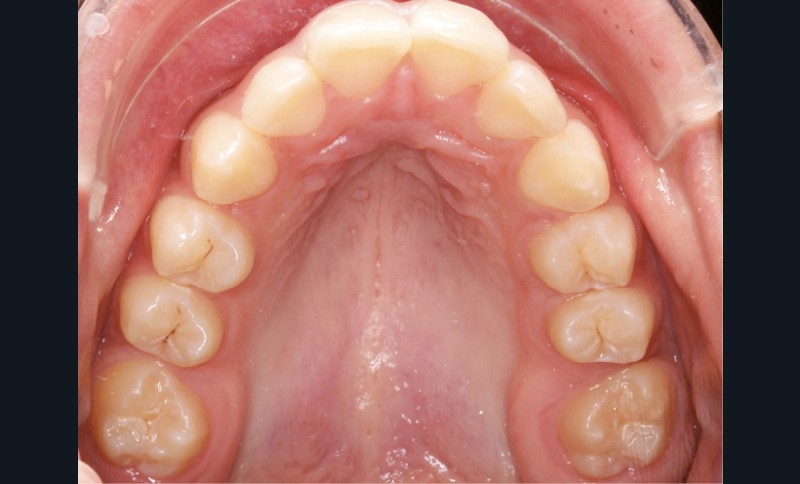

Examen endobuccal (fig. 2a-e)

L’hygiène est satisfaisante et le parodonte sain. On note aux deux arcades l’absence des premières molaires et la fermeture partielle des espaces d’extraction avec mésiorotation marquée de 17, 27 et 37. À la mandibule, l’encombrement antérieur est estimé à 2 mm et les espaces d’extraction résiduels à 12 mm.

Dans le sens transversal, malgré une occlusion correcte des secteurs latéraux, on observe une endoalvéolie maxillaire et une non-concordance des médianes incisives avec déviation de la médiane mandibulaire vers la droite. Le recouvrement incisif est normal.